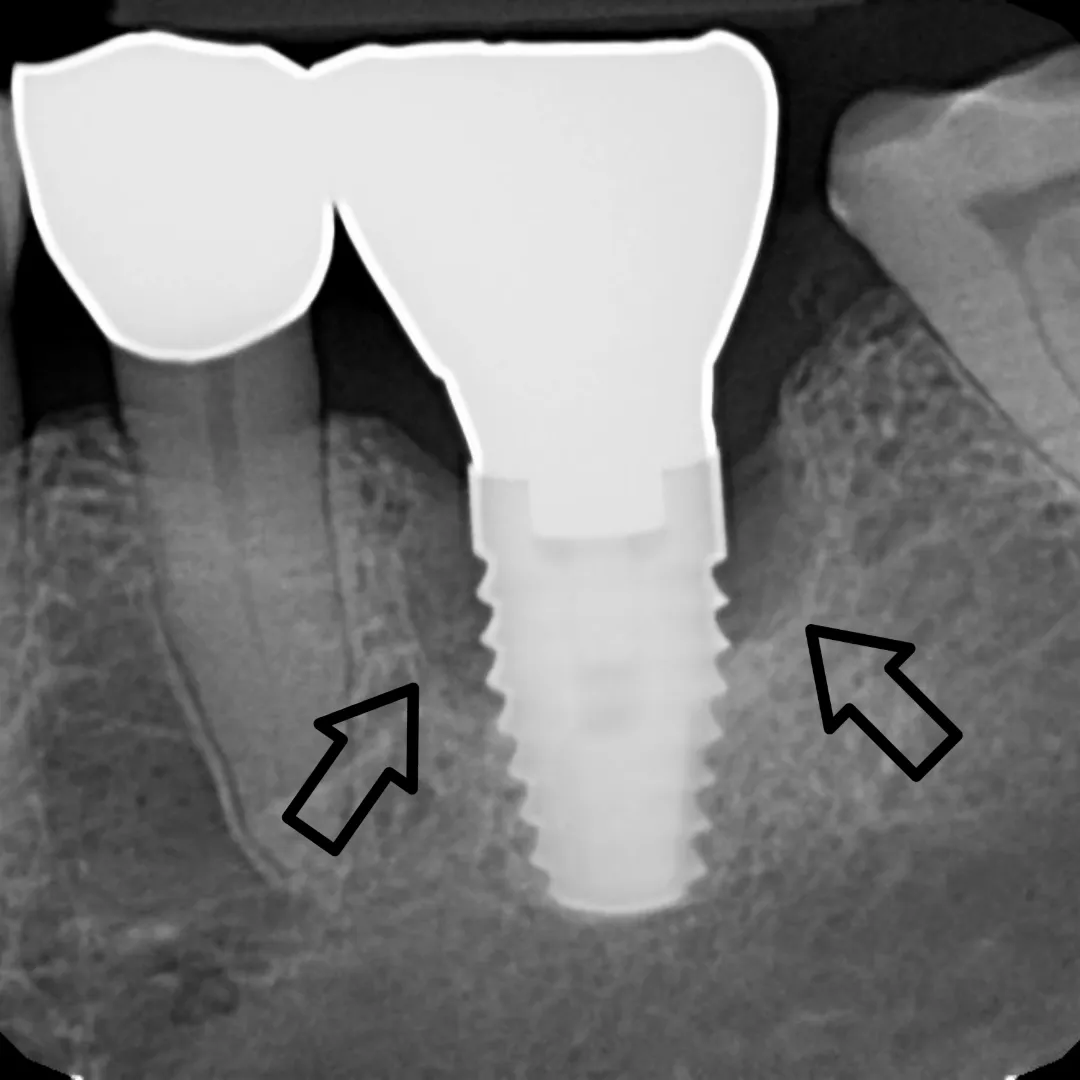

before

after